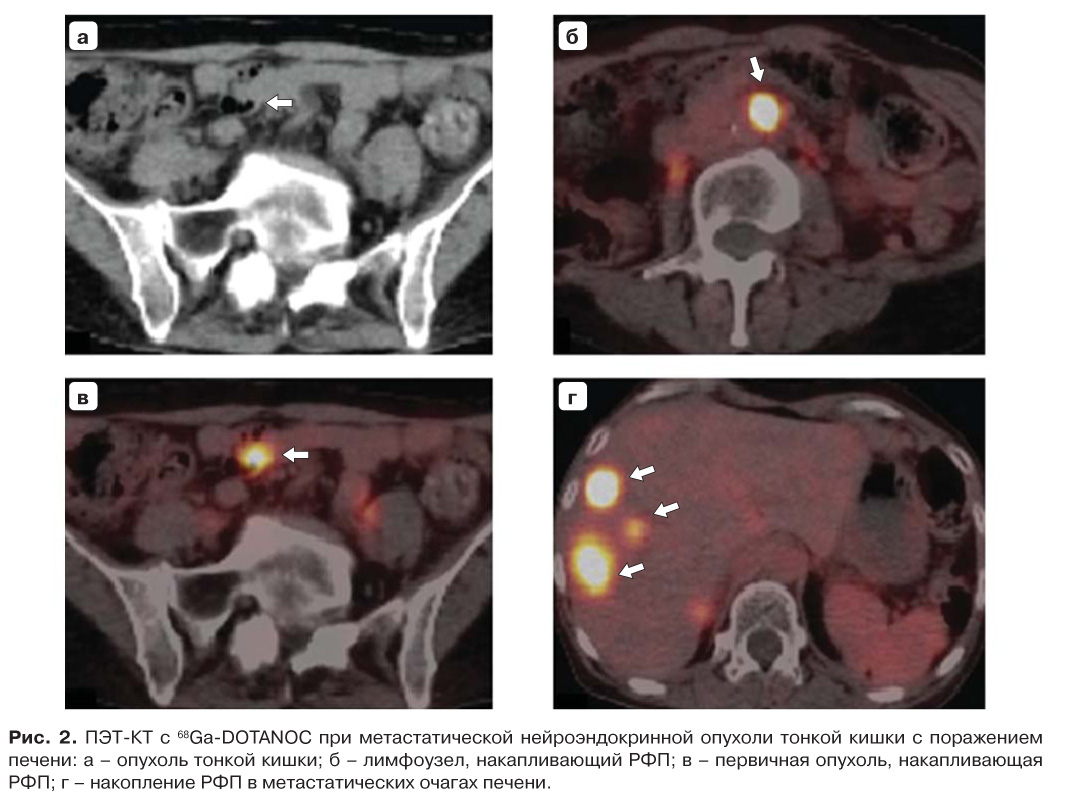

В функционально-топической диагностике НЭО хорошо зарекомендовала себя ПЭТ/КТ с октреотидом, меченным 68Ga, с хелатором DOTA: 68Ga-DOTATATE, 68Ga-DOTATOC и 68Ga-DOTANOC (рис. 2). Диагностическая информативность определяется степенью их аффинностик различным типам рецепторов соматостатина. 68Ga-DOTATATE высоко комплементарен рецепторам соматостатина 2-го типа, 68Ga-DOTATOC – рецепторам 2-го и 5-го типов, причем у первого аффинность к рецептору 2-го типа в 10 выше, чем у второго. 68Ga-DOTANOC связывается с рецепторами 2, 3 и 5-го типов. ПЭТ/КТ с 68Ga-DOTATOC и 68Ga-DOTATATE демонстрирует более высокую чувствительность (>90%) в выявлении НЭО по сравнению с ОФЭКТ/КТ с 111In-DTPA-октреотидом [63].

Рис. 2. ПЭТ-КТ с 68Ga-DOTANOC при метастатической нейроэндокринной опухоли тонкой кишки с поражением печени: а – опухоль тонкой кишки; б – лимфоузел, накапливающий РФП; в – первичная опухоль, накапливающая РФП; г – накопление РФП в метастатических очагах печени.